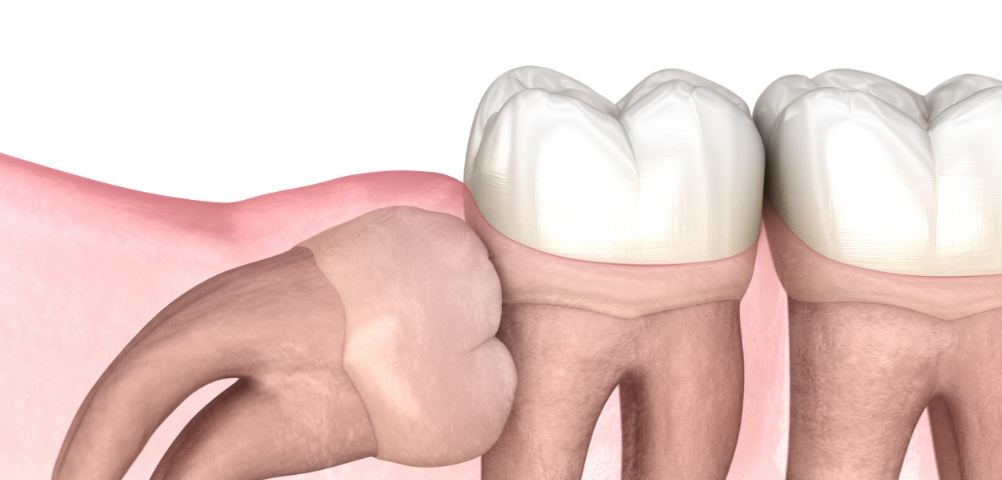

在通过锥形束CT精细确认智齿方向,

神经位置及与邻牙关系后,

仅在

确有必要的情况下才进行拔除

采用最大程度减少组

织损伤的方式来降低负担,

帮助患者更轻松地完成术后恢复